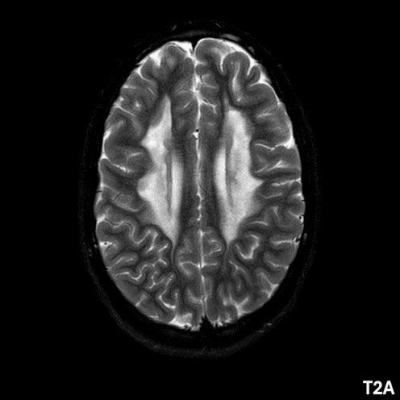

- A) Aksiyel T2A ve koronal T2A sekanslarda sentrum semiovale, korona radiata ve bazal ganglionlar düzeyinde bilateral frontoparietal derin periventriküler beyaz cevherde birleşme eğilimi gösteren hiperintens gliotik sinyal değişiklikleri (oklar) ve aksiyel T2A serilerde servikal spinal kordda posterior kolonda, lateral kesimlerde sinyal artımları (oklar) izlendi.

- B) Kontrastsız T1A serilerde tarifli alanlarda hipointens (oklar) görünüm izlendi. Kontrastlı T1A serilerde bu düzeyde (oklar) kontrastlanma artışı izlenmedi. Diffüzyon ağırlıklı serilerde belirgin diffüzyon kısıtlaması (oklar) görülmedi.

- LBSL, karakteristik radyolojik özelliklere sahiptir. MRG’de tipik olarak bilateral ve simetrik beyaz cevher sinyal değişiklikleri görülürken, subkortikal U lifleri, internal kapsülün posterior kolları, trigeminal sinir traktları, serebellum, korpus kallozumun spleniumu, medulla oblongata ve omurilikteki dorsal kolonlar ile lateral kortikospinal traktlar genellikle korunur.

- Etkilenen bölgelerde T1’de hipointens, T2/FLAIR’da hiperintens sinyal değişiklikleri izlenir. DWI’de lezyonların periferinde kısıtlı difüzyon görülebilir. MRS’de beyaz cevherde laktat artışı saptanabilir, ancak bu her hastada mevcut değildir.